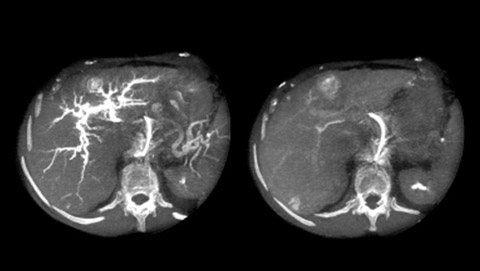

XperCT extends the capabilities of the interventional suite offering CT like imaging to visualize bone, soft tissue and vessels. This CT-like image can be acquired with or without contrast agent right in the angio suite and overlaid with the 3D vascular image. It helps identify subtle soft-tissue lesions and supports in room characterization in arterial and post-arterial phase.

XperCT extends the capabilities of the interventional suite offering CT like imaging to visualize bone, soft tissue and vessels in case of contrast enhanced acquisition. XperCT supports fast abdominal protocols with 5 to 8 seconds acquisition time for excellent image quality while significantly minimizing respiratory artifacts. The XperCT 3D volume is displayed automatically within 8 to 15 seconds after the acquisition and confirms selective targeting of hepatic lesion and helps avoid untargeted embolization and drug delivery.